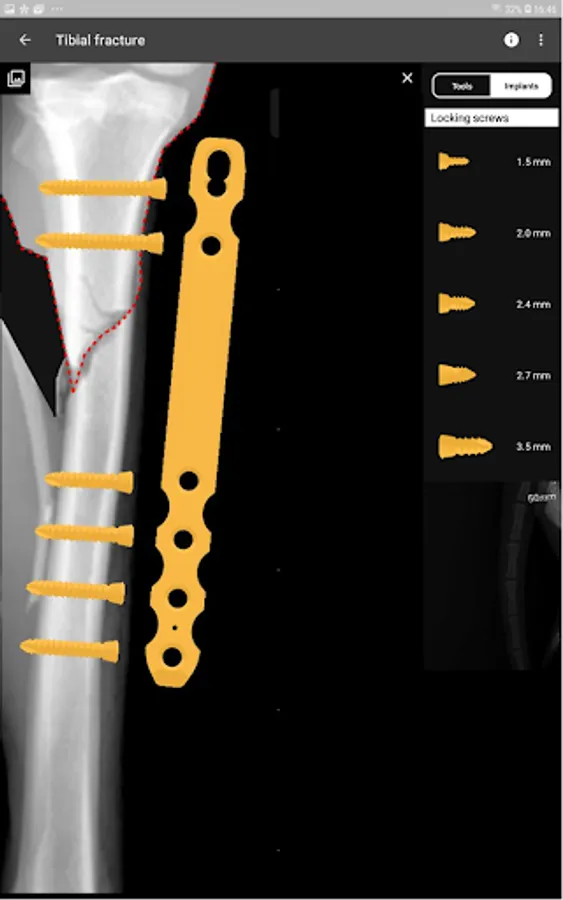

4. Catalogue of BETA Implants locking plates, in 2.0, 2.4, 2.7 and 3.5 sizes:

o) Locking screws